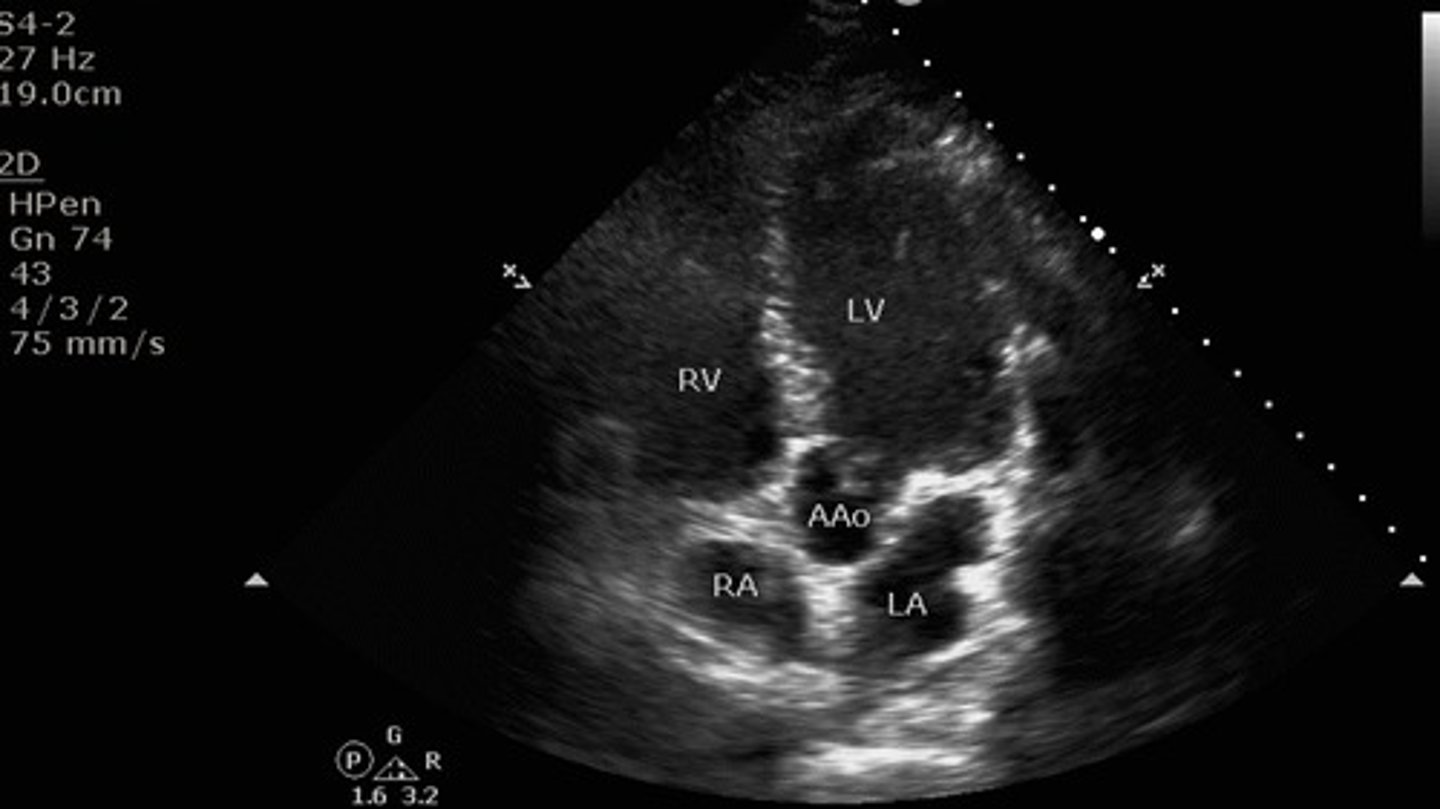

5 chamber apical view

what view is this?

the ascending aorta

what additional structure can you see when you achieve the 5 "chamber" view?

LV, RV, LA, RA, mitral valve, tricuspid valve, aortic valve

what structures are seen with apical 5 chamber view?